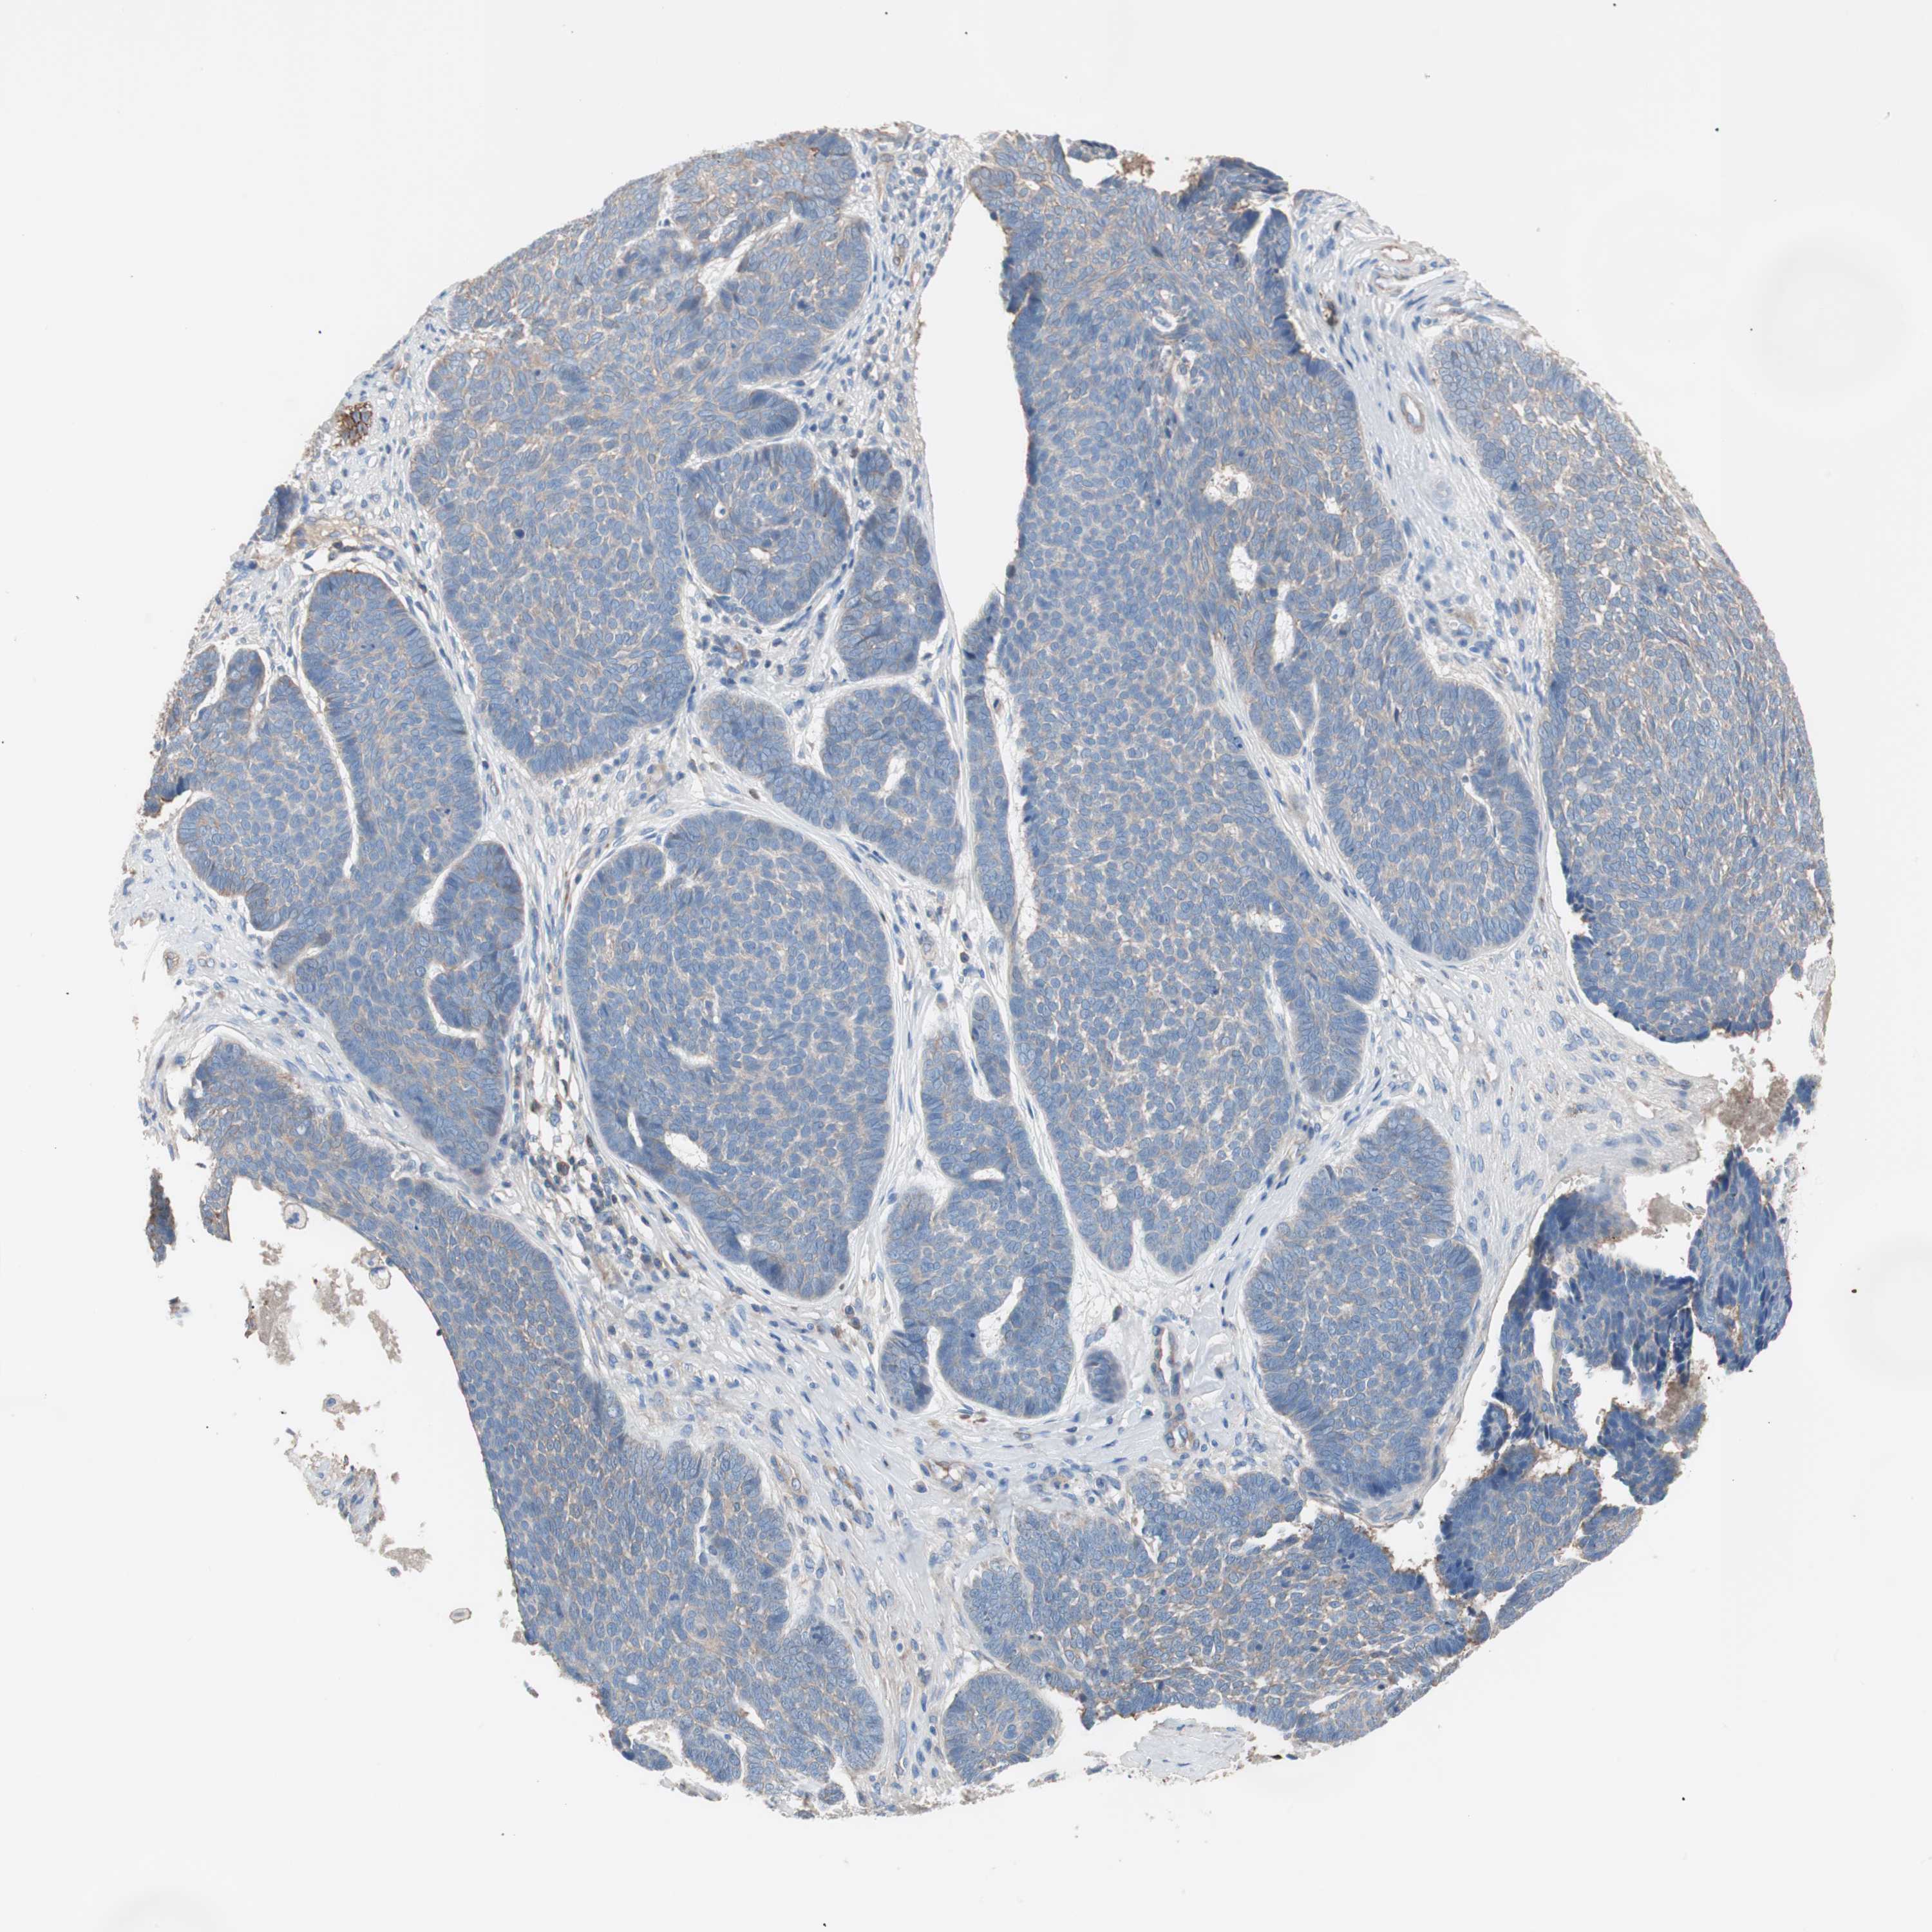

Antibody HPA006970

Staining

Low

Intensity

Weak

Quantity

<25%

Location

Cytoplasmic/membranous

Squamous cell carcinoma, metastatic, NOS